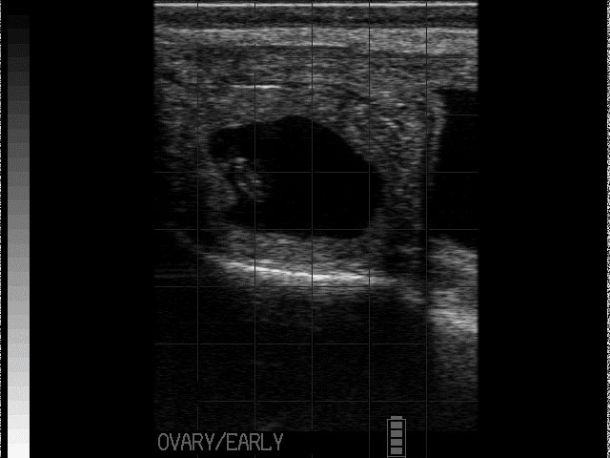

Detailed ultrasonography can detect pregnancy from 22-24 days post-insemination but due to higher rates of loss and inconsistency in quickly detecting the foetus, it is advisable that ultrasonographic pregnancy diagnosis at 28-30 days post-insemination is performed as it becomes very reliable (see Photo 2)2. At this point, the embryo becomes visible as a small, echogenic (white) structure suspended within the black (anechoic) uterine fluid2. Beyond this point, ageing is performed by either measuring or ‘eyeballing’ foetal crown-rump length, head or trunk diameter, head length or eyeball diameter (for references lengths see Table 1)6,7. Modern ultrasound machines will automatically give an estimated days in-calf, if the image is frozen and a distance is measured, but the author finds that the grid function (where a box represents 10mm) is a more useful way to eyeball these measurements without having to freeze the image. Thus thinking in boxes allows the user to reliably age using the crown rump length up to day 60 and then using head diameter and/or eyeball from days 60-150 days (see Photo 3). Measuring the placentomes is not a very reliable method to accurately age owing to the fact that placentome size will vary depending on where in the horn it is located, with smaller placentome being at the edge of the horns2.